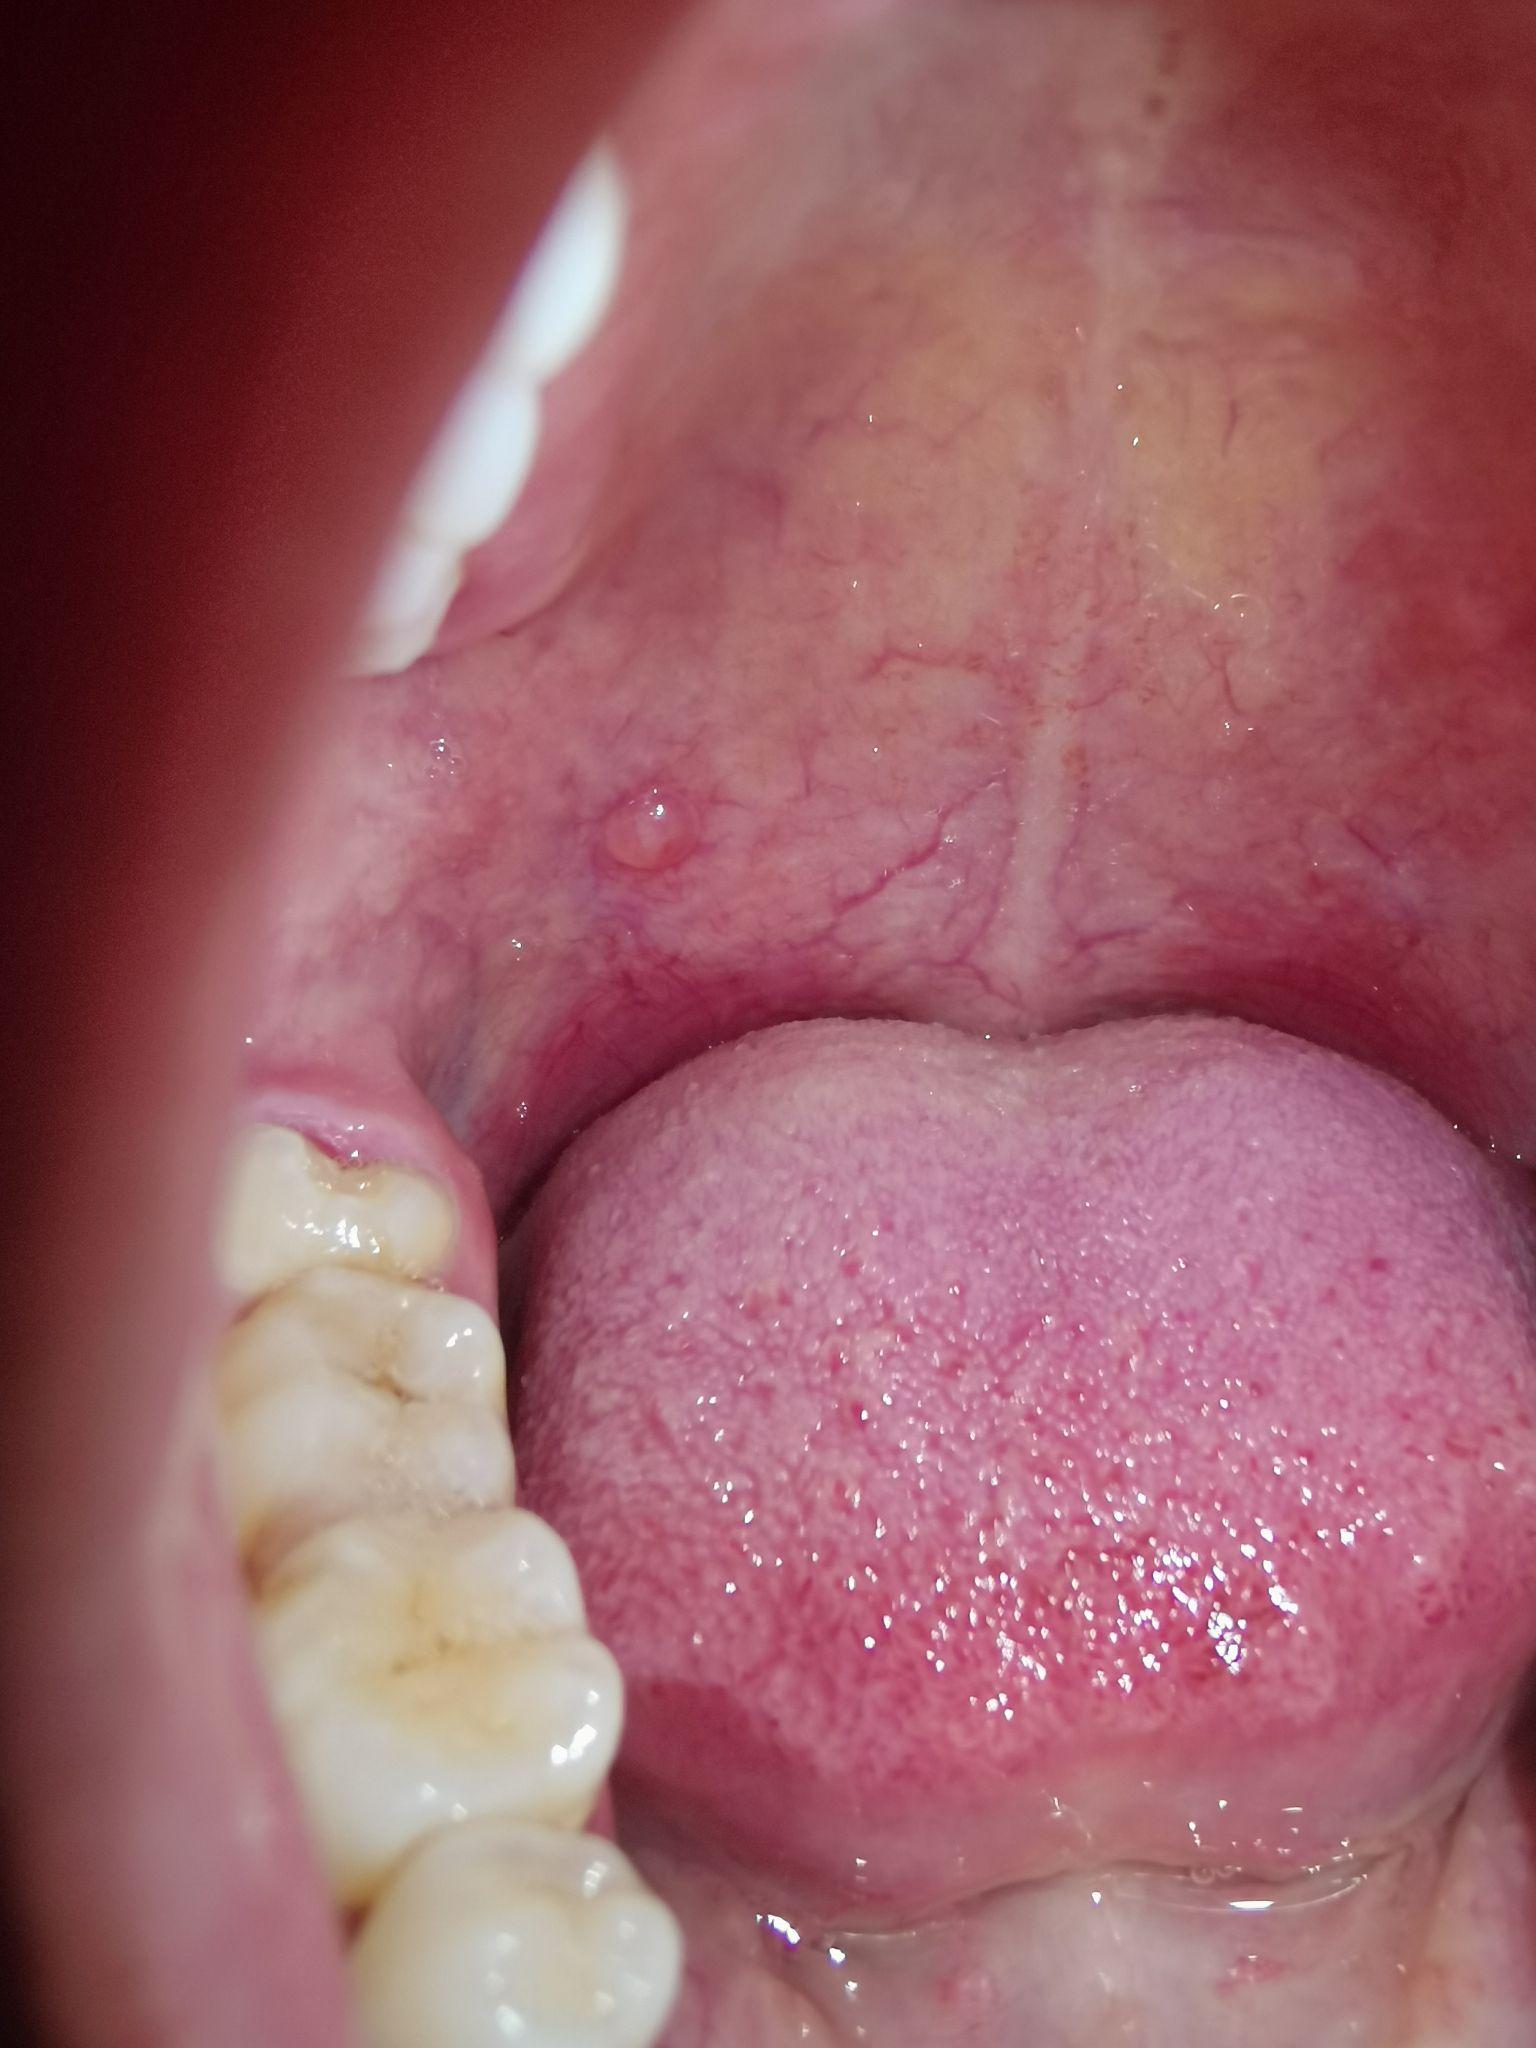

口腔上颚长了个大红包,大半年了怎么回事? - 知乎